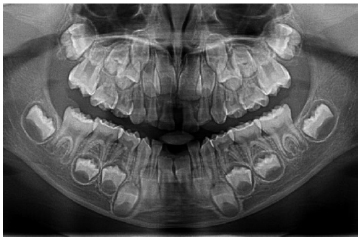

At the 2021 follow-up, when the patient was 9 years old and in the mixed dentition stage, oral examination indicated moderate oral hygiene. Clinically, the eruption sequence of permanent teeth appeared age-appropriate. A panoramic radiograph confirmed these findings, showing localized vertical bone loss adjacent to the mandibular central incisors, while the remaining dentition displayed normal eruption patterns without other pathological changes (Fig. 2). Professional cleaning and scaling were performed. Preventive measures were reinforced, including topical fluoride application and placement of sealants on the permanent first molars, aiming to enhance caries resistance during the mixed dentition phase.

Panoramic radiograph at age 9 (2021), showing localized vertical alveolar bone loss adjacent to the mandibular central incisors, with the remaining dentition demonstrating a normal eruption sequence.